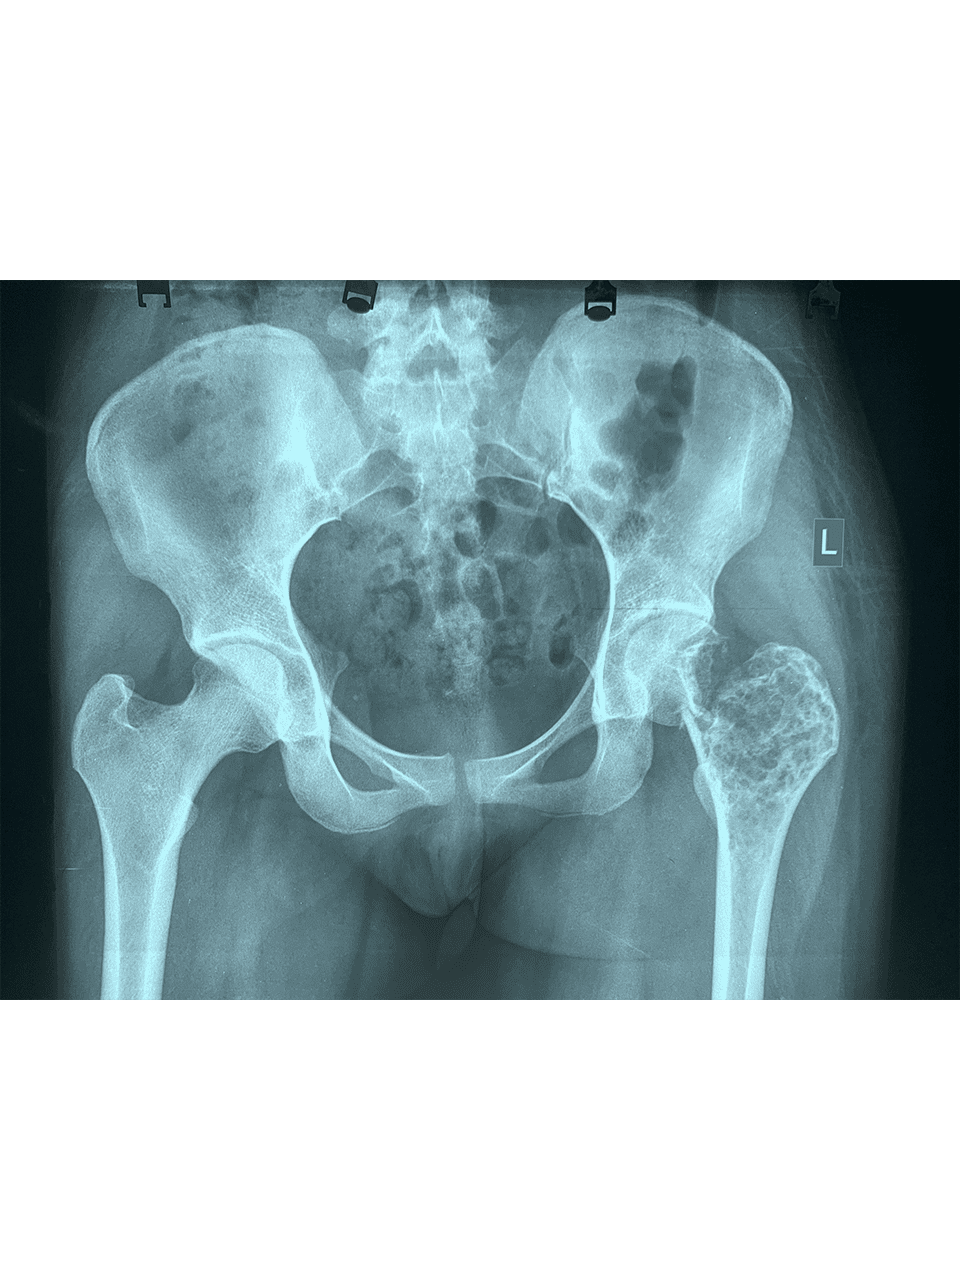

Dr. Weber and his partners participate in short term medical mission trips to Cambodia. Dr. Weber has had the pleasure of going twice now in 2018 and 2020. During these trips Dr. Weber performs total hip replacements on patients who normally would have no treatment options. To learn more and to see videos from the experience please click the links below.